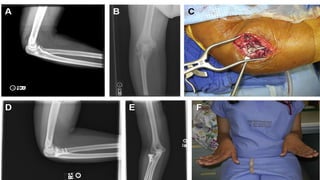

External fixators have also

been used to restore and

stabilize a congruent

elbow articulation and

facilitate early motion

Recurrent Elbow Instability External fixators havealso been used to restore and stabilize a congruent elbow articulation and facilitate early motion